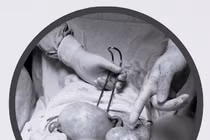

Kíp mổ khoa Ngoại phối hợp với khoa Gây mê hồi sức thực hiện phẫu thuật. Qua đường rạch nhỏ ổ bụng, phẫu thuật viên khéo léo bóc tách khối u buồng trứng phải kích thước 10 cm, đồng thời cầm máu. Sau hơn 1 giờ, ca mổ diễn ra thuận lợi. Khối u buồng trứng phải đã được bóc tách, cắt bỏ trọn vẹn và đưa ra ngoài.

Nhỏ tuổi song khối u khá lớn nên các phẫu thuật viên đã thực hiện bóc tách tỉ mỉ, lấy u ra nguyên vẹn với vết mổ tối thiểu, hạn chế ảnh hưởng đến cơ thể bé còn đang phát triển. Khâu gây mê và chuẩn bị trước mổ cũng được thực hiện cẩn trọng, đảm bảo ca mổ an toàn, hiệu quả”.